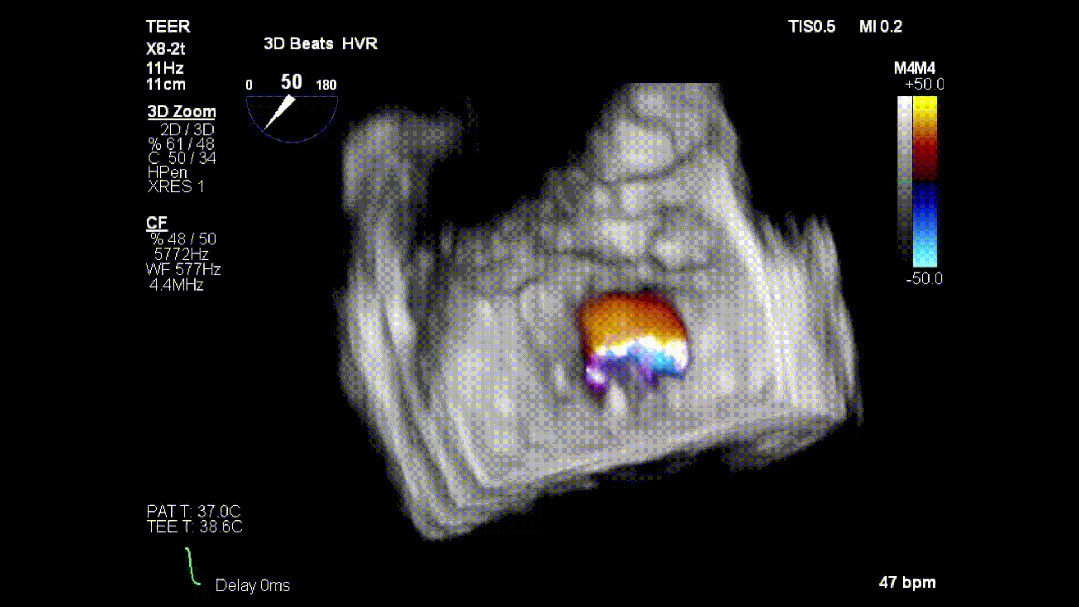

本次培训的“重头戏”—— 两台高难度 TEER 手术沉浸式观摩,将培训氛围推向高潮。手术病例分别为 “P2 宽大脱垂病变” 与 “早期 Barlow 病变”,由厦门大学心血管病医院团队与浙江大学附属邵逸夫医院团队协同完成。术中,专家团队操作精准、配合默契,不仅完美展现了 TEER 技术在复杂病例中的应用优势,更通过实时讲解,让学员直观掌握手术关键步骤、解剖评估要点与应急处理思路。

病例1:

病例2: